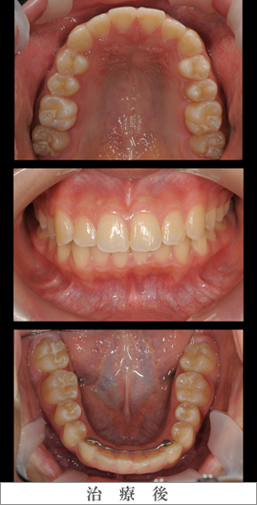

急速拡大装置

写真左列:治療開始前の上下前歯部のスペース不足

写真中列:急速拡大装置装着直後

写真右列:保定期間を入れ7ヶ月後の拡大終了時